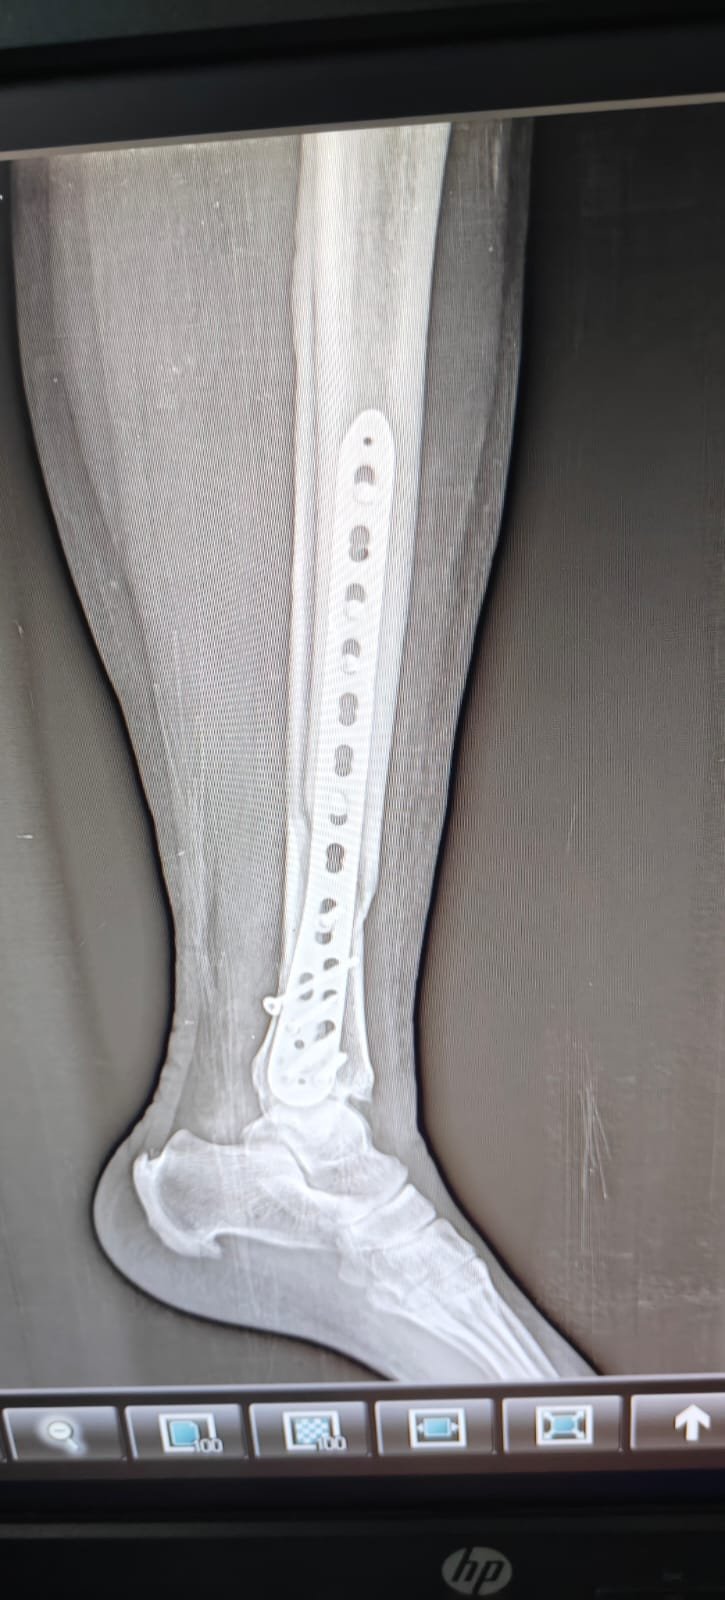

- Fracture Treatment